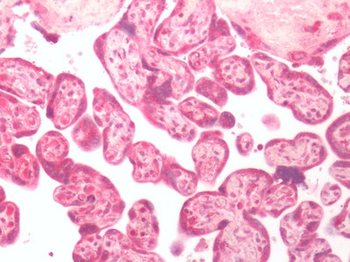

| Tested Applications | IHC |

| Dilution range | IHC: 1/25-1/50; ELISA: 1/5000-1/10000 |

| Reactivity | Human, Mouse, Rat |